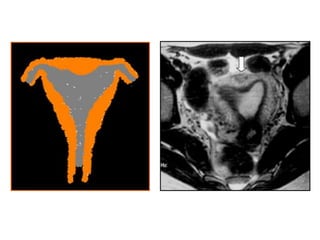

Clasificación

American Fertility Society

CLASE I Agenesia o hipoplasia

CLASE II Útero unicorne

CLASE III Útero didelfo

CLASE IV Útero bicorne

CLASE V Útero septado

CLASE VI Útero arcuato

CLASE VII Asociadas a DES